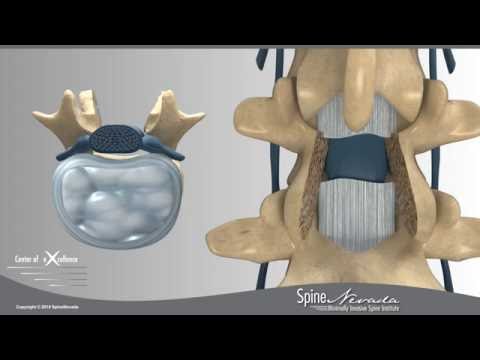

Przednia foraminotomia szyjna

Na filmie doktor Pakzaban prezentuje przednią foraminotomię szyjną z użyciem Bone Scalpel.